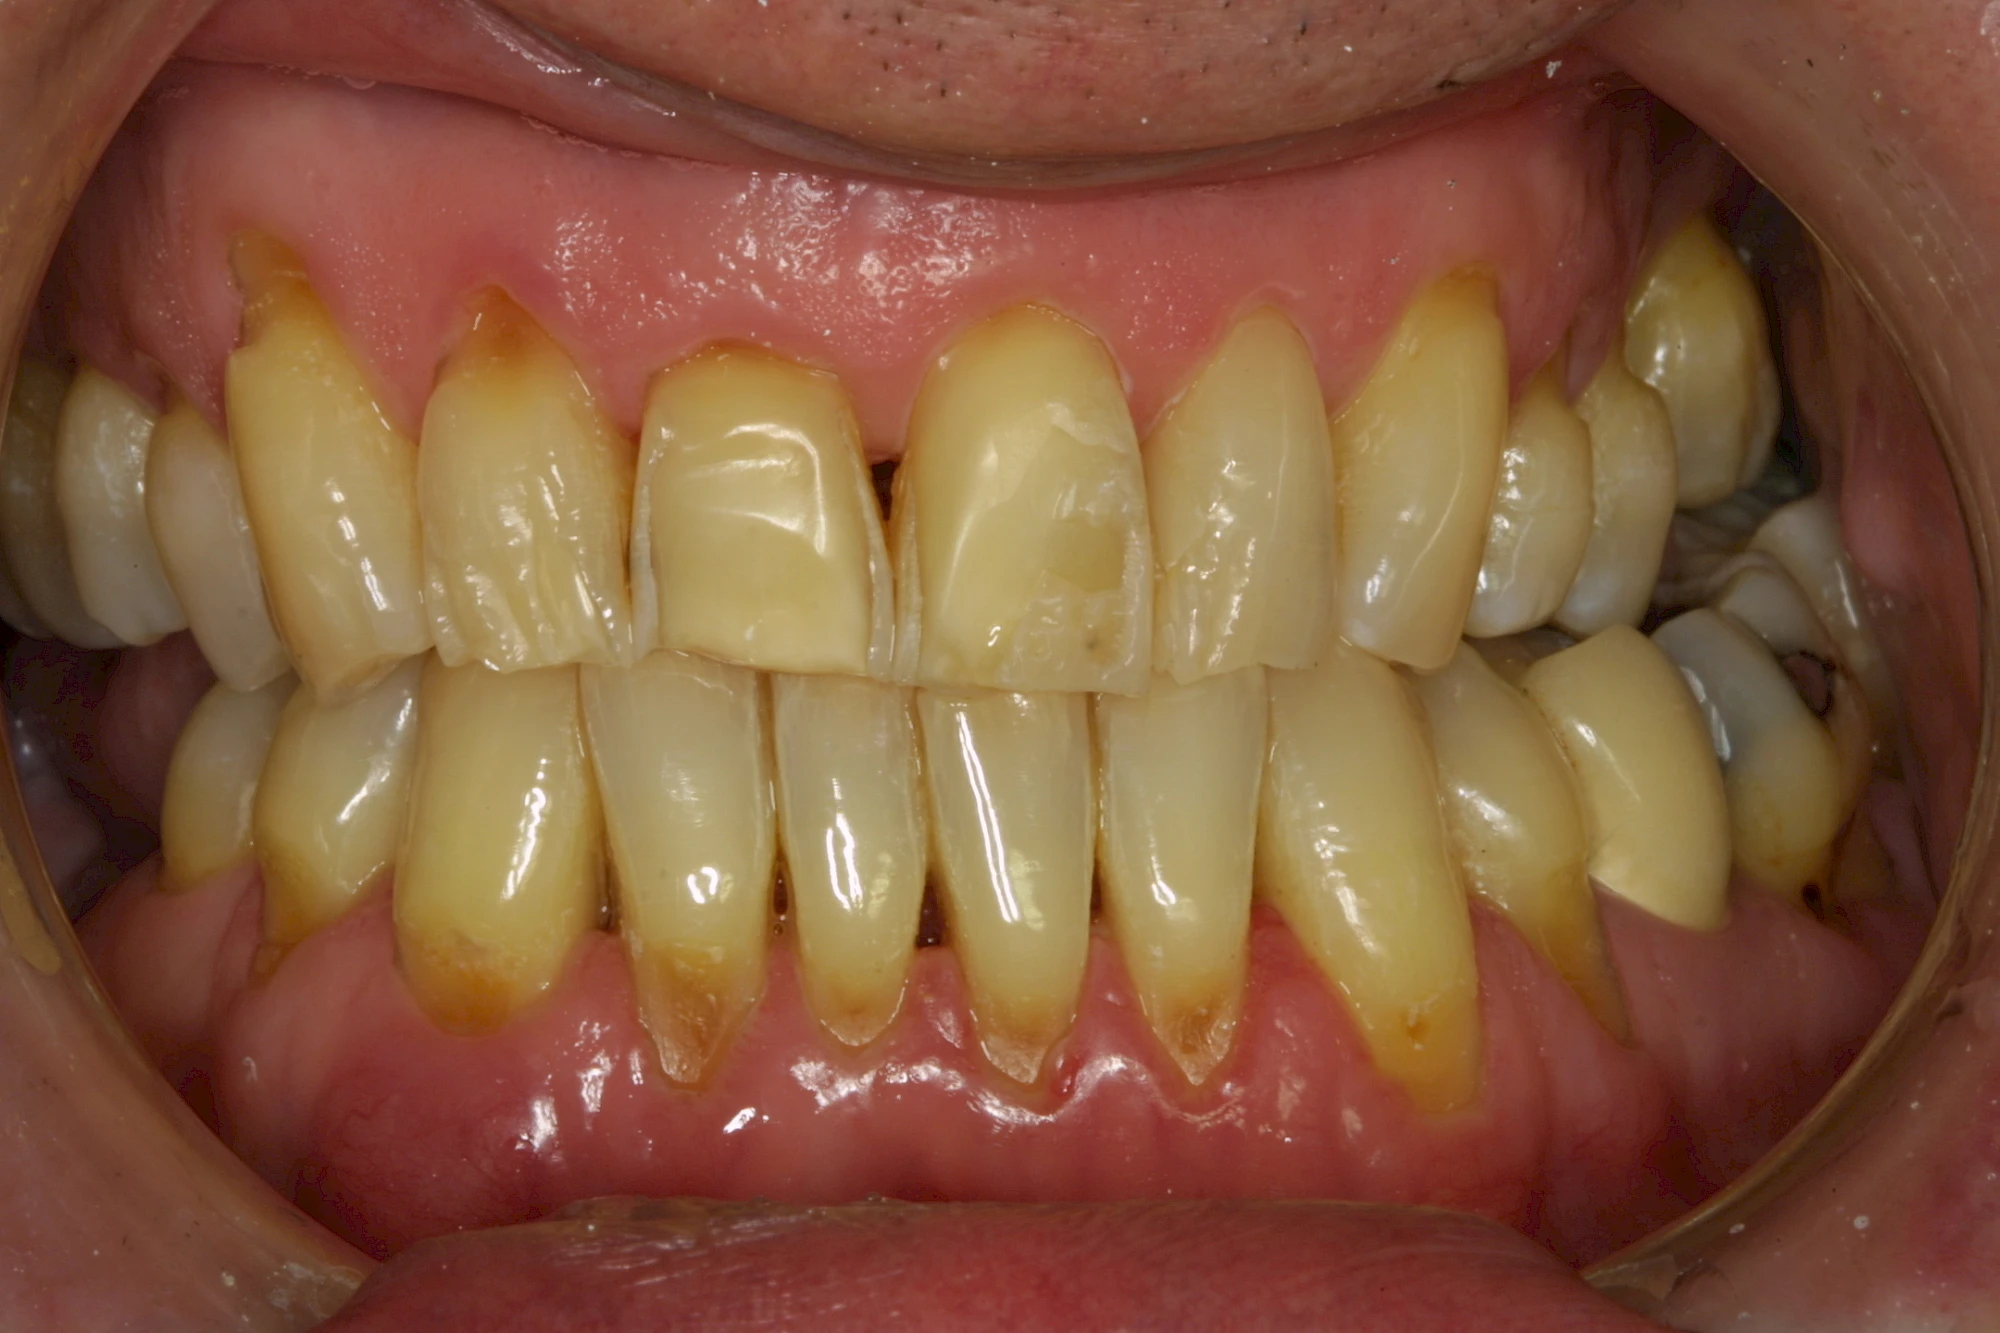

Auswaschung (Erosion) dagegen ist eine Verschleißerscheinung der Zähne aufgrund von immer wiederkehrenden Säureangriffen durch die Nahrung, verstärkt zum Beispiel durch den Genuss säurehaltiger Getränke oder Speisen. Auch bei Menschen mit einer Essstörung (z. B. Bulimie) können die Zähne durch die Magensäure ausgewaschen erscheinen.